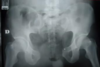

2

5

3

How well did you know this?